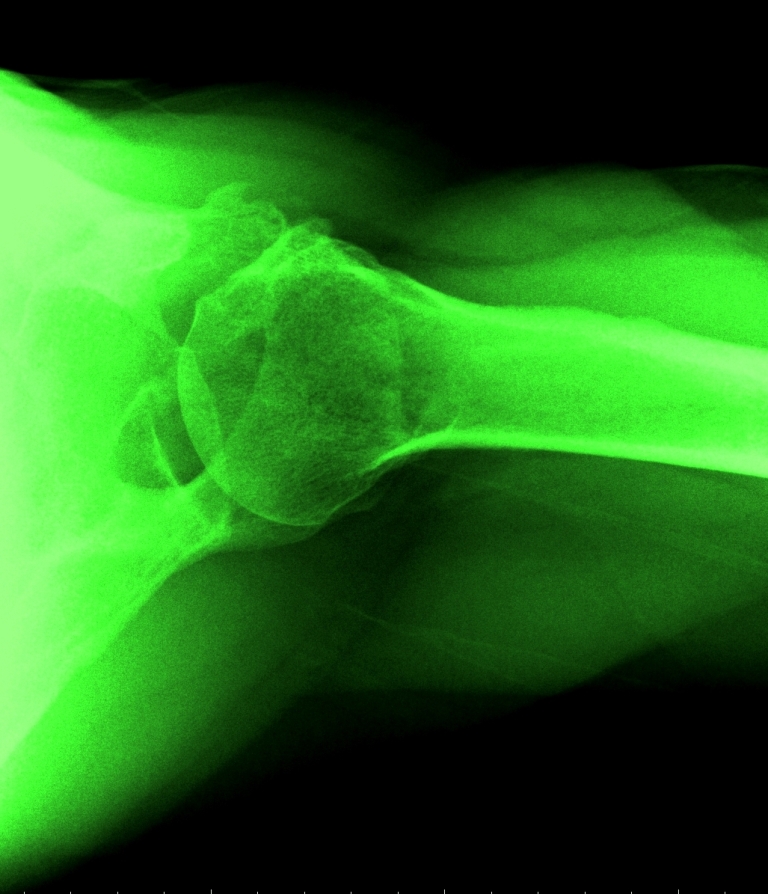

Best of all, the X-ray shoulder views are available, and simple photo-editing software–Paint and Microsoft Office Picture Manager–may be used on the images. Andy Warhol did stuff like this the hard way, back in the day. Longer ago, Robert Rauschenberg had to content himself with light-reactive paper and bright, bright light for some white-on-blue skinscapes of him and his companion. But now–colorizing, brightness&contrast, data compression and many other image-manipulative techniques are easy as pie, funfunfun, and available with the latest operating systems!

So here are four shoulderscapes. If time were not of the essence I would have happily spent another several hours playing with the image; alas, time is scarce. These four, though, demonstrate how color, contrast and cropping of the same subject matter might yield four quite different visual payoffs.